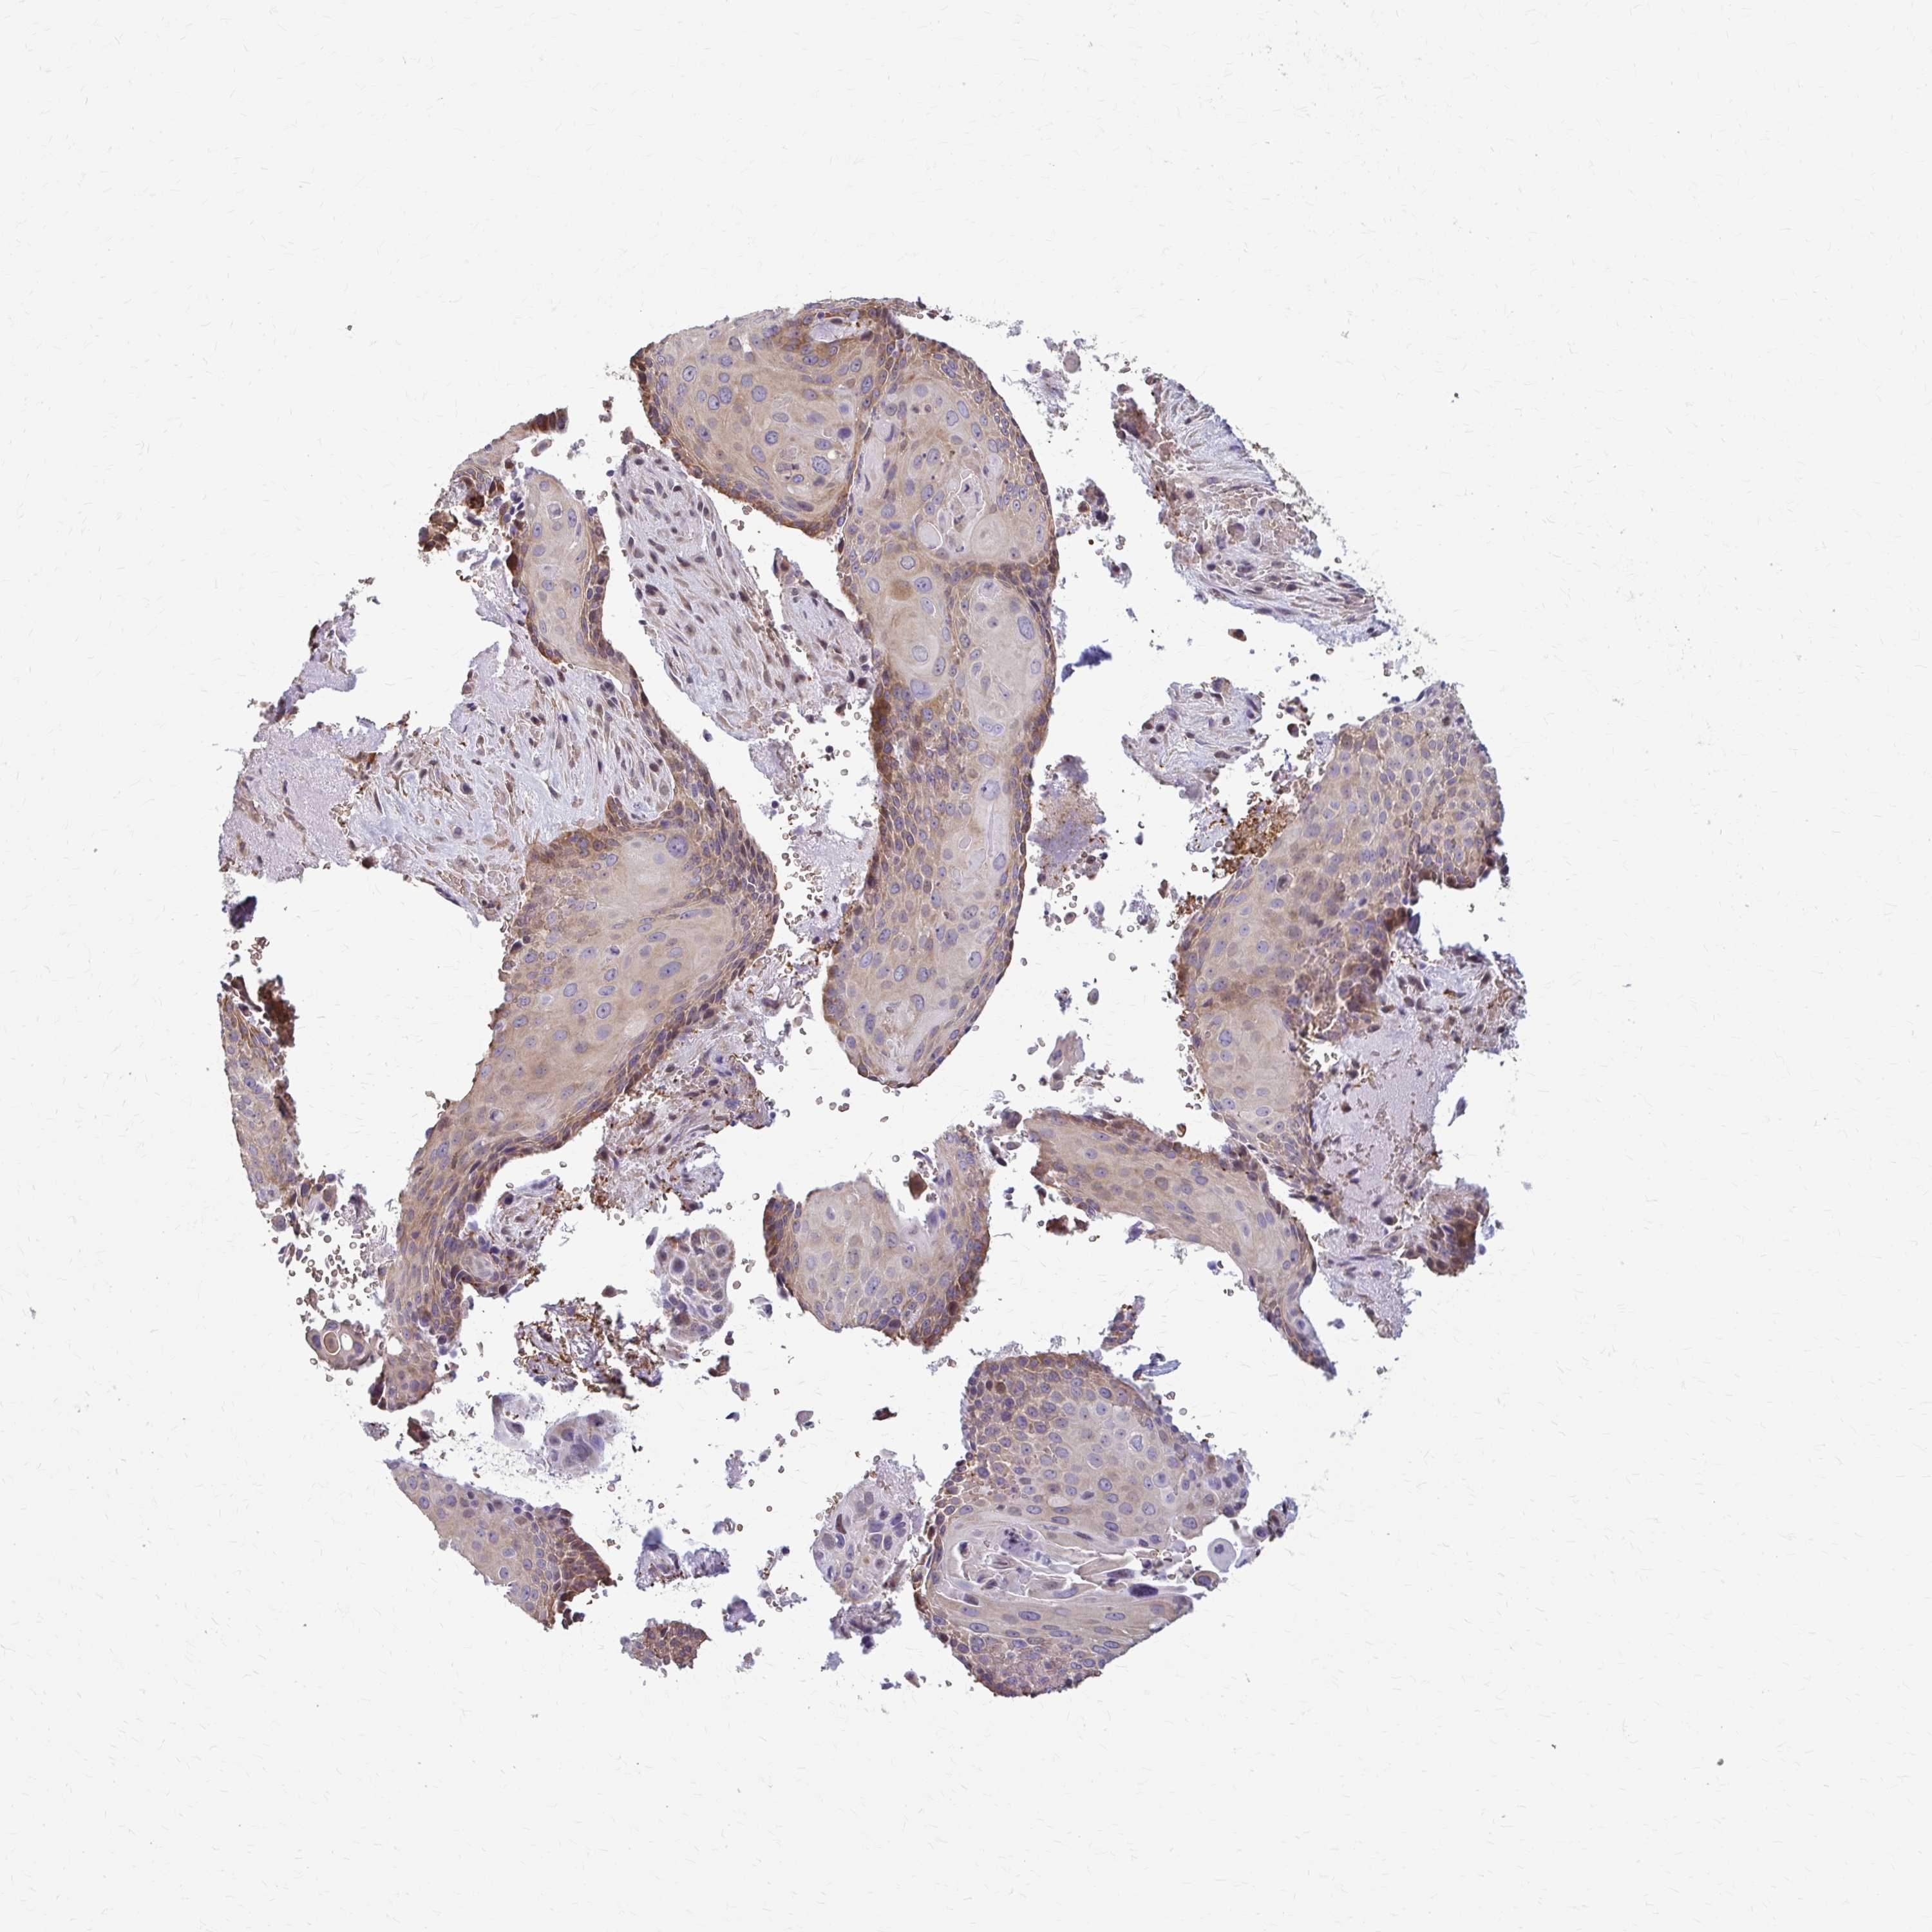

CERVICAL CANCER - Protein expressioni

A mouse-over function shows sample information and annotation data. Click on an image to view it in a full screen mode. Samples can be filtered based on level of antibody staining by selecting one or several of the following categories: high, medium, low and not detected. The assay and annotation is described here.

Note that samples used for immunohistochemistry by the Human Protein Atlas do not correspond to samples in the TCGA dataset.

Antibody stainingi

Antibody staining in the annotated cell types in the current human tissue is reported as not detected, low, medium, or high, based on conventional immunohistochemistry profiling in selected tissues. This score is based on the combination of the staining intensity and fraction of stained cells.

Each image is clickable and will lead to virtual microscopy that enables deeper exploration of all samples and also displays staining intensity scores, fraction scores and subcellular localization as well as patient and tissue information for each sample.

Antibody HPA060755

Staining

High

Medium

Low

Not detected

Intensity

Strong

Moderate

Weak

Negative

Quantity

>75%

75%-25%

<25%

None

Location

Nuclear

Cytoplasmic/membranous

Cytoplasmic/membranous,nuclear

Squamous cell carcinoma, NOS